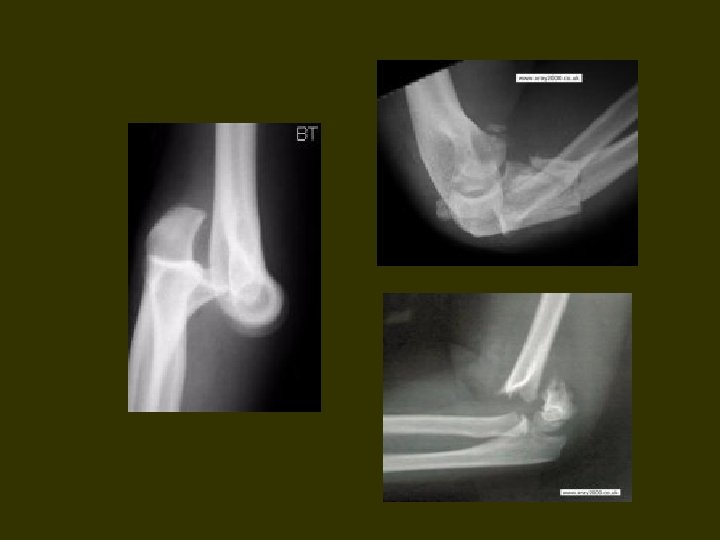

Elbow region

Anterior elbow Surface anatomy Three eminences Two grooves Elements Lateral groove - v. cephalica, n. cutaneus antebrachii lateralis Medial groove – v. basilica, n. cutaneus antebrachii medialis V. mediana cubiti

Deep structures А. Muscles Flexors of forearm – medial eminence Extensors of forearm – lateral eminence Brachial muscles, mm. biceps, brachialis – middle eminence

Deep structures B. Vessels and nerves Medial bundle - between m. biceps brachii and pronator teres - a. v. brachialis, n. medianus Lateral bundle - between m. brachialis and brachioradialis - n. radialis, a. collateralis radialis, a. recurrens radialis C. Cubital fossa Boundaries - m. brachioradialis (lateral), m. pronator teres (medial) Content - tendo m. brachialis, m. biceps brachii, bursa bicipitoradialis

Layers of the elbow Venous 1 v. cephalica 2 v. basilica 3 v. mediana cubiti Apponeurotic 1 aponeurosis bicipis 2 tendo m. biceps brachii

Neurovascular 1 a. brachialis 2 n. medianus Muscle 1 m. supinator 2 m. brachialis 3 tendo m. biceps brachii Bone 1 humerus 2 radius 3 ulna